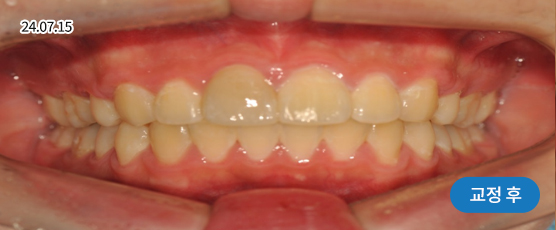

덧니교정 Solution

덧니는 악궁 크기, 얼굴형, 골격 등을 고려해 발치, 비발치를 현명하게 판단하여 치료합니다.

치아가 정렬될 공간을 확보하기 위해, 경우에 따라 소구치(작은 어금니)를 발치할 수 있습니다.

* 본 사진은 동일 조건에서 촬영되었으며, 환자 본인의 동의를 얻어 게재되었습니다.